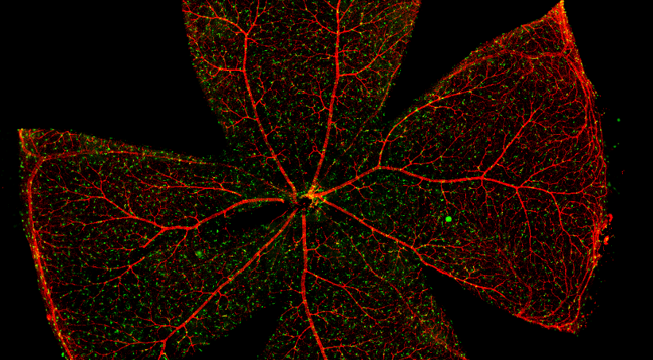

一般而言,眼底图像通常都是通过激光扫描成像进行采集,但是由于眼底可观测的视野往往是很有限的,一个患者的眼底信息需要多张扫描图像才能完全显示出来。这种局限性大大不利于病情进行全面的、细致的诊断。Tissue Cytometry全景组织流式定量分析技术进行全景图像获取,在单细胞、组织结构、细胞空间信息等多个层面进行定位、定性、定量分析。从而更好的对病变区域进行有针对性的跟踪观察和全面分析。

视网膜荧光样本中小胶质细胞胞体、神经纤维识别、血管识别、血管斑点识别、神经元与血管的距离分析。

1. 利用TissueFAXS系统进行玻片荧光的全景扫描。

2. 使用StrataQuest分析软件进行定量分析。

5. 识别血管的Texa Red染色区域面积及强度。

血管识别:根据Texa Red通道进行识别,并去除面积小的及非同一焦面的血管,仅对确定的清晰的同一焦面的大血管进行面积统计。